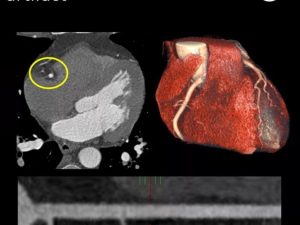

At the forefront of the demonstration is Philips AI-powered echocardiography platform, which introduces first-to-market tools such as automated 3D tricuspid valve quantification and 3D color flow quantification to assist in diagnosing mitral regurgitation. Philips will also debut its AI-enabled cardiovascular ultrasound platform, which accelerates cardiac ultrasound analysis. Additionally, the AI-enabled Spectral CT 7500 will showcase advanced cardiac imaging with reduced diagnostic time, while Philips collaboration with MyoStrain offers early detection of heart failure using MRI technology. Philips innovative solutions aim to provide clinicians with the tools needed for faster, more accurate diagnosis and treatment, improving patient outcomes in the fight against cardiovascular disease.